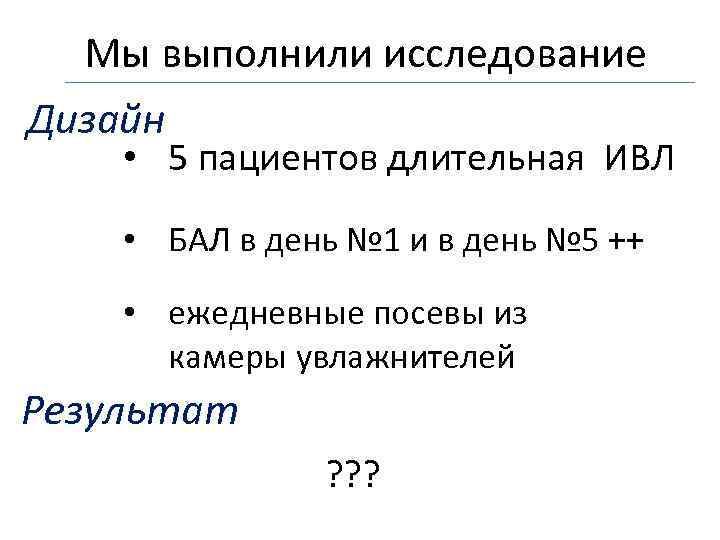

Мы выполнили исследование Дизайн • 5 пациентов длительная ИВЛ • БАЛ в день № 1 и в день № 5 ++ • ежедневные посевы из камеры увлажнителей Результат ? ? ?

Мы выполнили исследование Дизайн • 5 пациентов длительная ИВЛ • БАЛ в день № 1 и в день № 5 ++ • ежедневные посевы из камеры увлажнителей Результат ? ? ?